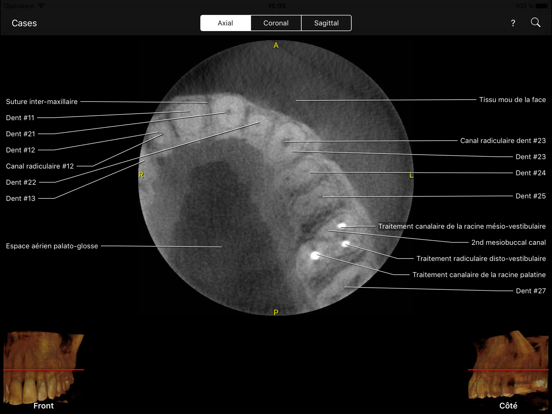

L’application CBCT permet aux cliniciens, résidents et étudiants en médecine dentaire d’apprendre les repères anatomiques de la même façon comme s’ils regardaient le volume via le logiciel de visualisation de données CBCT mais avec tous les repères visibles et animées sur toutes les vues MPR.

Le niveau d'interactivité et de visualisation est sans précédent. Cette application étonnante couvre des centaines de points de repère anatomiques visibles sur des volumes CBCT de petite à moyenne à grand champ de vue (FOV). Il vous permet également de tester vos connaissances à travers le mode test, ce qui est très "cool". Vous pouvez également rechercher un point d'intérêt ou le retrouver à partir d'une liste alphabétique et l'application vous l’indiquera.

- Plans de vue axial, frontal et sagittal.